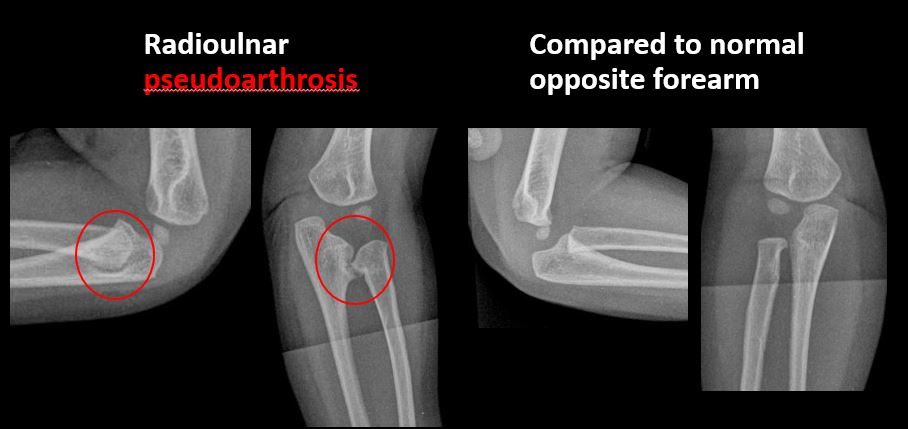

The joint is widened, narrowed, dislocated, malaligned, or incongruent. [Yes/No]

There is pseudoarthrosis. [Yes/No]